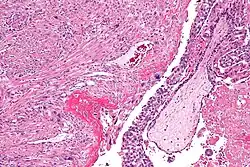

Môle hydatiforme complète

La môle hydatiforme complète survient lorsque l’ADN de la mère disparaît complètement après la fécondation et qu’il y a doublement de l’ADN du père. En l'absence d'ADN maternel, le fœtus ne se forme pas et un tissu ressemblant à une grappe de raisin se développe.